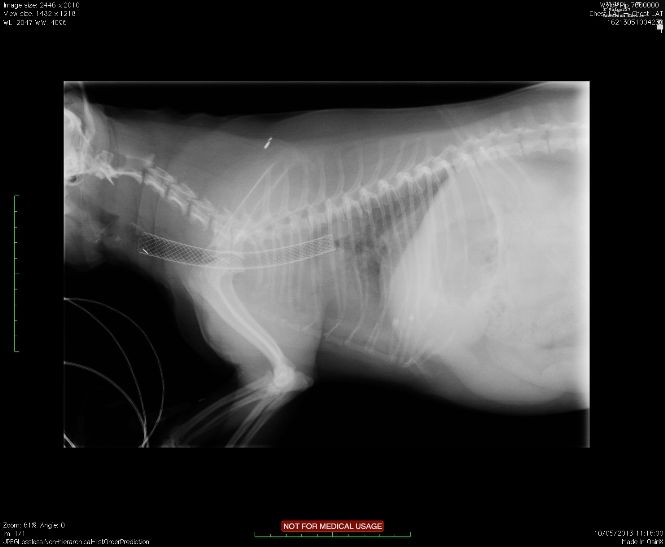

Pip a 10 year old Yorkie was referred for treatment. He was having severe problems with tracheal collapse, especially in the heat. Pip had an especially designed stent deployed to treat severe tracheal collapse. The little Yorkshire Terrier had an unusually tapered trachea and so a stent had to be custom made and shipped transatlantically to give him the best chance of a good long term outcome. We all hope he goes on to make a full recovery, so far so good!

Lateral thoracic radiograph showing postoperative appearance of deployed intra-tracheal stent